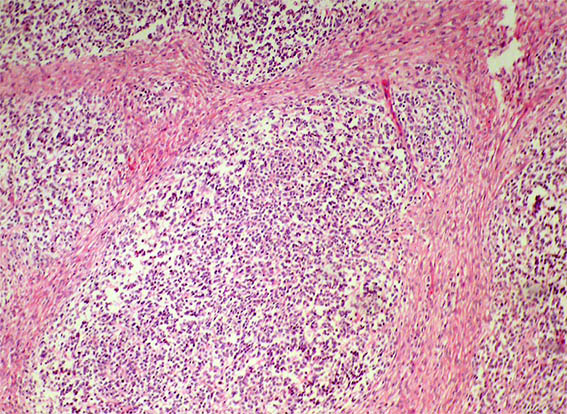

Figure 1.

H&E, X100.